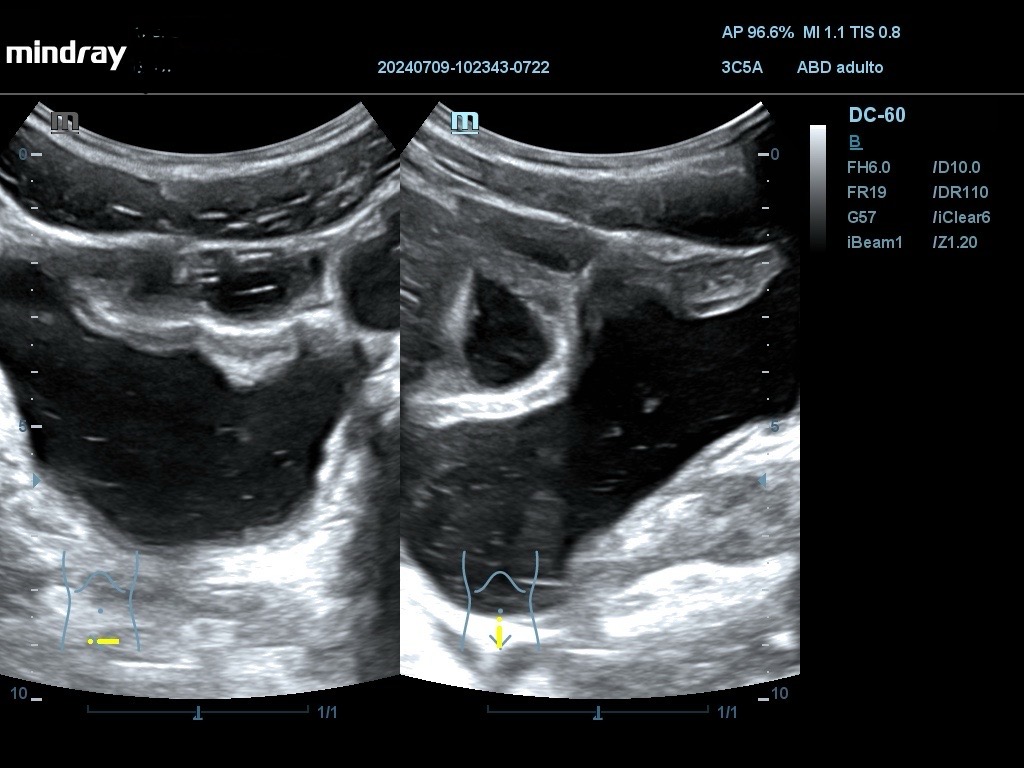

Ecografía: Se han observado varias imágenes poco habituales en vejiga urinaria: imágenes hiperecogénicas flotantes sin sombra posterior, móviles (detritus), engrosamiento de pared vesical que simula una vejiga no distendida con áreas anecoicas, pared con imagen en doble carril, masa vesical.

La sospecha inicial por criterios epidemiológicos es esquistosomiasis con afectación de vejiga urinaria. El diagnóstico diferencial se debe hacer con otras infecciones y tumores (raros en esta edad). En uno de los casos, AE considera que las imágenes se deben a vejiga poco replecionada y no las valora como patológicas. La masa vesical podría ser de tipo inflamatorio o tumoral.